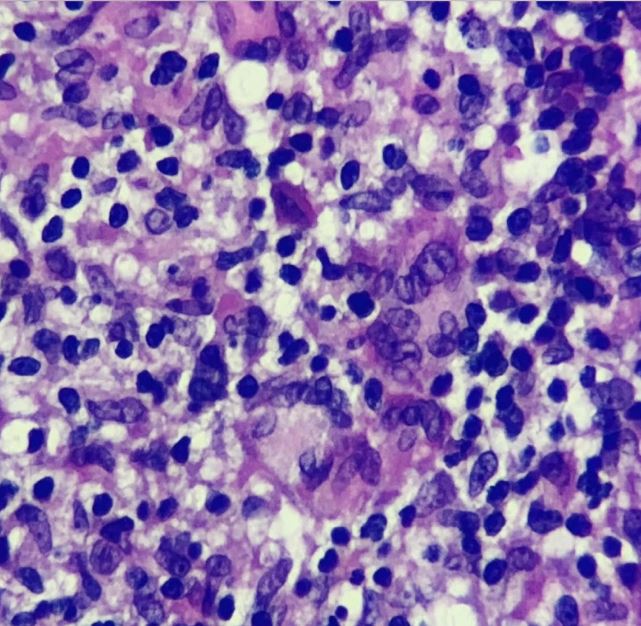

CASO CLÍNICO. Leishmaniasis mucocutánea de aspecto lupoide

Zuleta P y col.

La leishmaniasis es una zoonosis causada por protozoos intracelulares del género Leishmania spp.

En este trabajo, los autores presentan el caso de una paciente de 41 años, oriunda de Tucumán, con una forma poco frecuente de leishmaniasis mucocutánea (LMC). La clínica mostró placas infiltradas con tubérculos centrofaciales y compromiso mucoso. La histología reveló un infiltrado inflamatorio granulomatoso y la PCR confirmó Leishmania spp.

Se indicó tratamiento con antimoniato de meglumina y pentoxifilina, con reducción posológica por efectos adversos y evolución clínica favorable.

Los autores concluyen que este caso resalta la importancia de considerar variantes crónicas lupoides en el diagnóstico diferencial de la LMC y la necesidad de una correlación clínico-histopatológica.

Infiltrado inflamatorio constituido por células gigantes multinucleadas e histiocitos conformando granulomas (HyE, 400x)